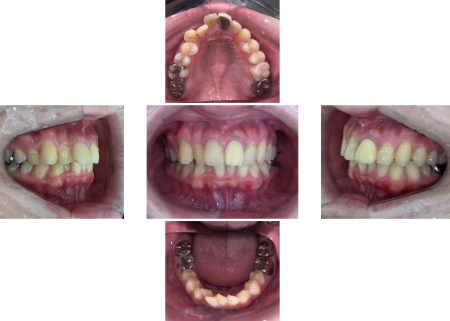

拝見したところ、上下の前歯が前後に重なり合っている「叢生(そうせい)」で、部分的に歯がねじれている「捻転(ねんてん)」がありました。

右上の前歯(側切歯/2番)が内側にずれて生えているため、隣の前歯(犬歯/3番)が飛び出ているようにみえる状態でした。

患者様は「英語の講師をしていて、『th』を発音する時に舌が遠い感じがする」とのことでした。